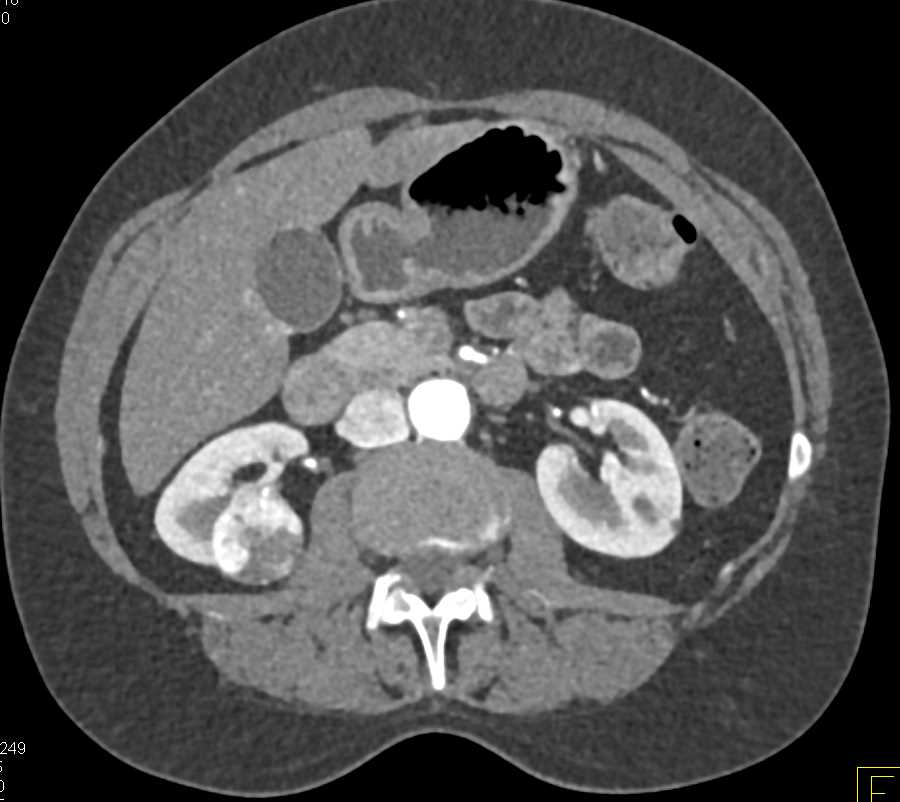

Clear Cell Renal Cell Carcinoma (CCRCC) Simulates an Oncocytoma